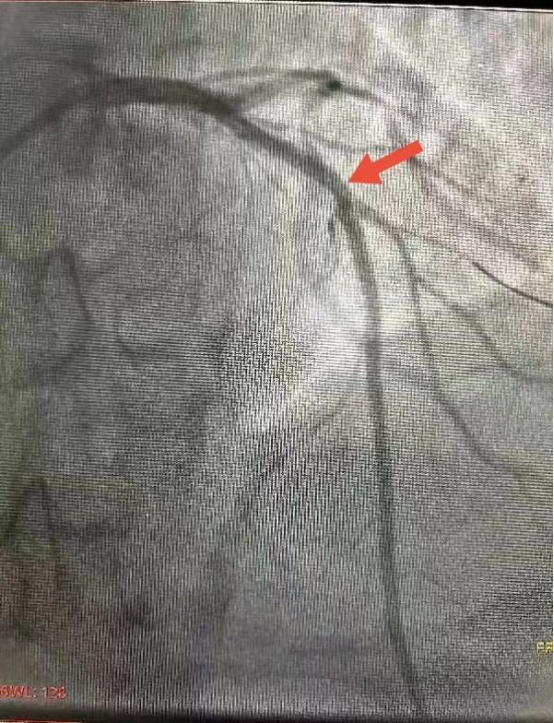

充分考虑到手术难度及风险,李宁主任团队经术前会诊讨论后决定选用目前国际上最先进的振波球囊技术预处理病变后置入支架。经过6个周期,共计60次的振波治疗,钙化病变及狭窄血管段顺利松解,充分恢复血流后,顺利置入心脏支架2枚。术中术后患者无特殊不适症状,无并发症出现,现已康复出院。

△术后造影